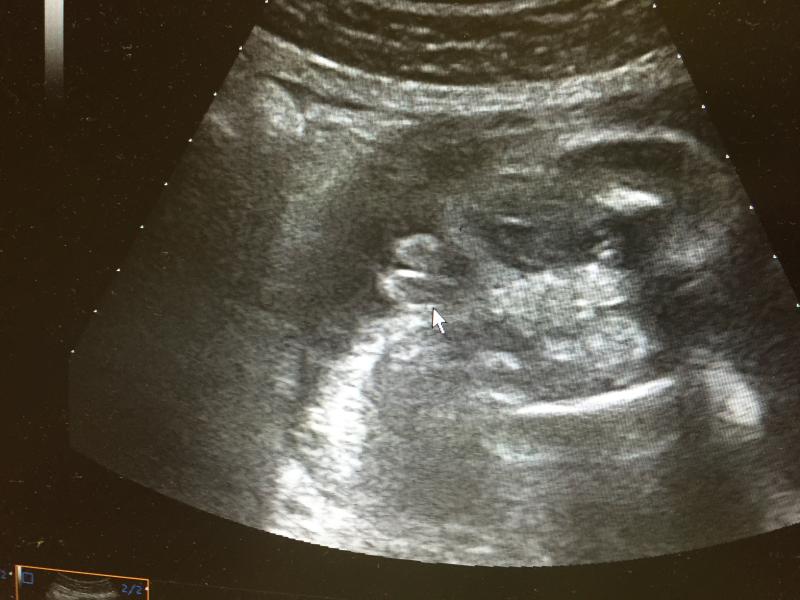

Ну вот наша любовь показала кто есть кто! Муж и мама ржут говорят на яйца похоже,а не на губы!А мне прям обидно,это же девочка!

@ohhsasha, нет,на 20 неделе предположили девочку,на 25 мальчик,а на 33 девочка.Как то так.

@yamipolli, и правда, позже тоже схожу для доп.подтверждения)) а то после того как мне сказали мальчик, сделали просто фото головы в профиль, так мои родственники кричали так где ж тут краник???🤦♀️🤦♀️🤦♀️